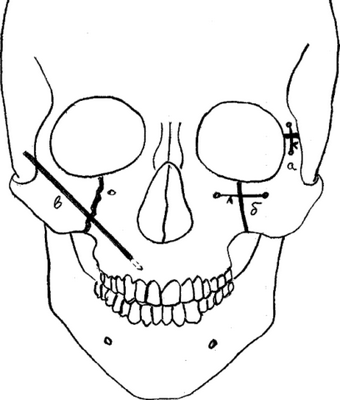

Ортогнатические операции выполняют при остеотомии верхней челюсти, когда проводятся внутриротовые костные разрезы над зубами и ниже обеих глазниц, позволяющие переместить верхнюю челюсть, включая небо и верхний ряд зубов. Такое перемещение позиционируют при помощи заранее изготовленной специальной шины, которая будет надежно гарантировать ее правильное положение нижней челюсти по отношению к мягким тканям.

Остеотомия верхней челюсти

В процессе проведения манипуляции, хирург делает надрезы костных внутриротовых тканей, расположенных в зоне глазниц и верхней частью зубного ряда.

Такой шаг позволяет доктору беспрепятственно двигать верхнюю челюсть с зубными фрагментами и небным участком. Челюсть устанавливают в заданное положение и крепят посредством специальной каппы.

Верхняя челюсть. Выполняется путем костных внутриротовых тканей. Специалист устанавливает челюсть в заданное положение и крепит посредством специальных конструкций. В завершении производится антисептическая обработка и зашивание десен.